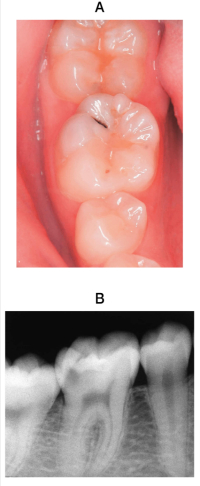

15 歳の男子。下顎右側第一大臼歯の違和感を主訴として来院した。歯髄電気診に生活反応を示すが、打診痛はない。初診時の口腔内写真とエックス線画像を別に示す。

適切な対応はどれか。1つ選べ。

a. 経過観察

b. フッ化物歯面塗布

c. ボンディング材によるコーティング

d. 修復処置

e. 抜髄